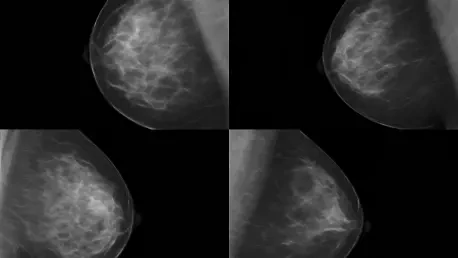

Your study found that women in their 80s who get regular mammograms have better outcomes. Can you explain what ‘better outcomes’ really means for these patients?

Sure. ‘Better outcomes’ primarily refers to detecting breast cancer at an earlier stage, which is often less aggressive and easier to treat. In our study, women who were screened typically had stage 1 or 2 cancers, compared to more advanced tumors in those who weren’t screened. Beyond early detection, this translated to higher survival rates—a 74% lower risk of dying from breast cancer among screened women. It’s not just about living longer, though; it’s about maintaining a better quality of life through less invasive treatments, which I’m happy to dive into further.

The numbers in your study are striking—a 55% lower risk of cancer returning and a 74% lower risk of dying for screened women. Why do these figures stand out to you?

Honestly, these numbers were surprising even to us. We knew screening would likely show benefits, but the magnitude of the difference was remarkable. A 74% lower risk of death highlights just how powerful early detection can be, even in an older population where other health issues might complicate outcomes. Compared to younger age groups, where survival benefits are well-documented, these stats suggest that the impact of screening doesn’t diminish with age as much as we might have assumed. It’s a strong argument for not arbitrarily stopping mammograms based on a birthday.